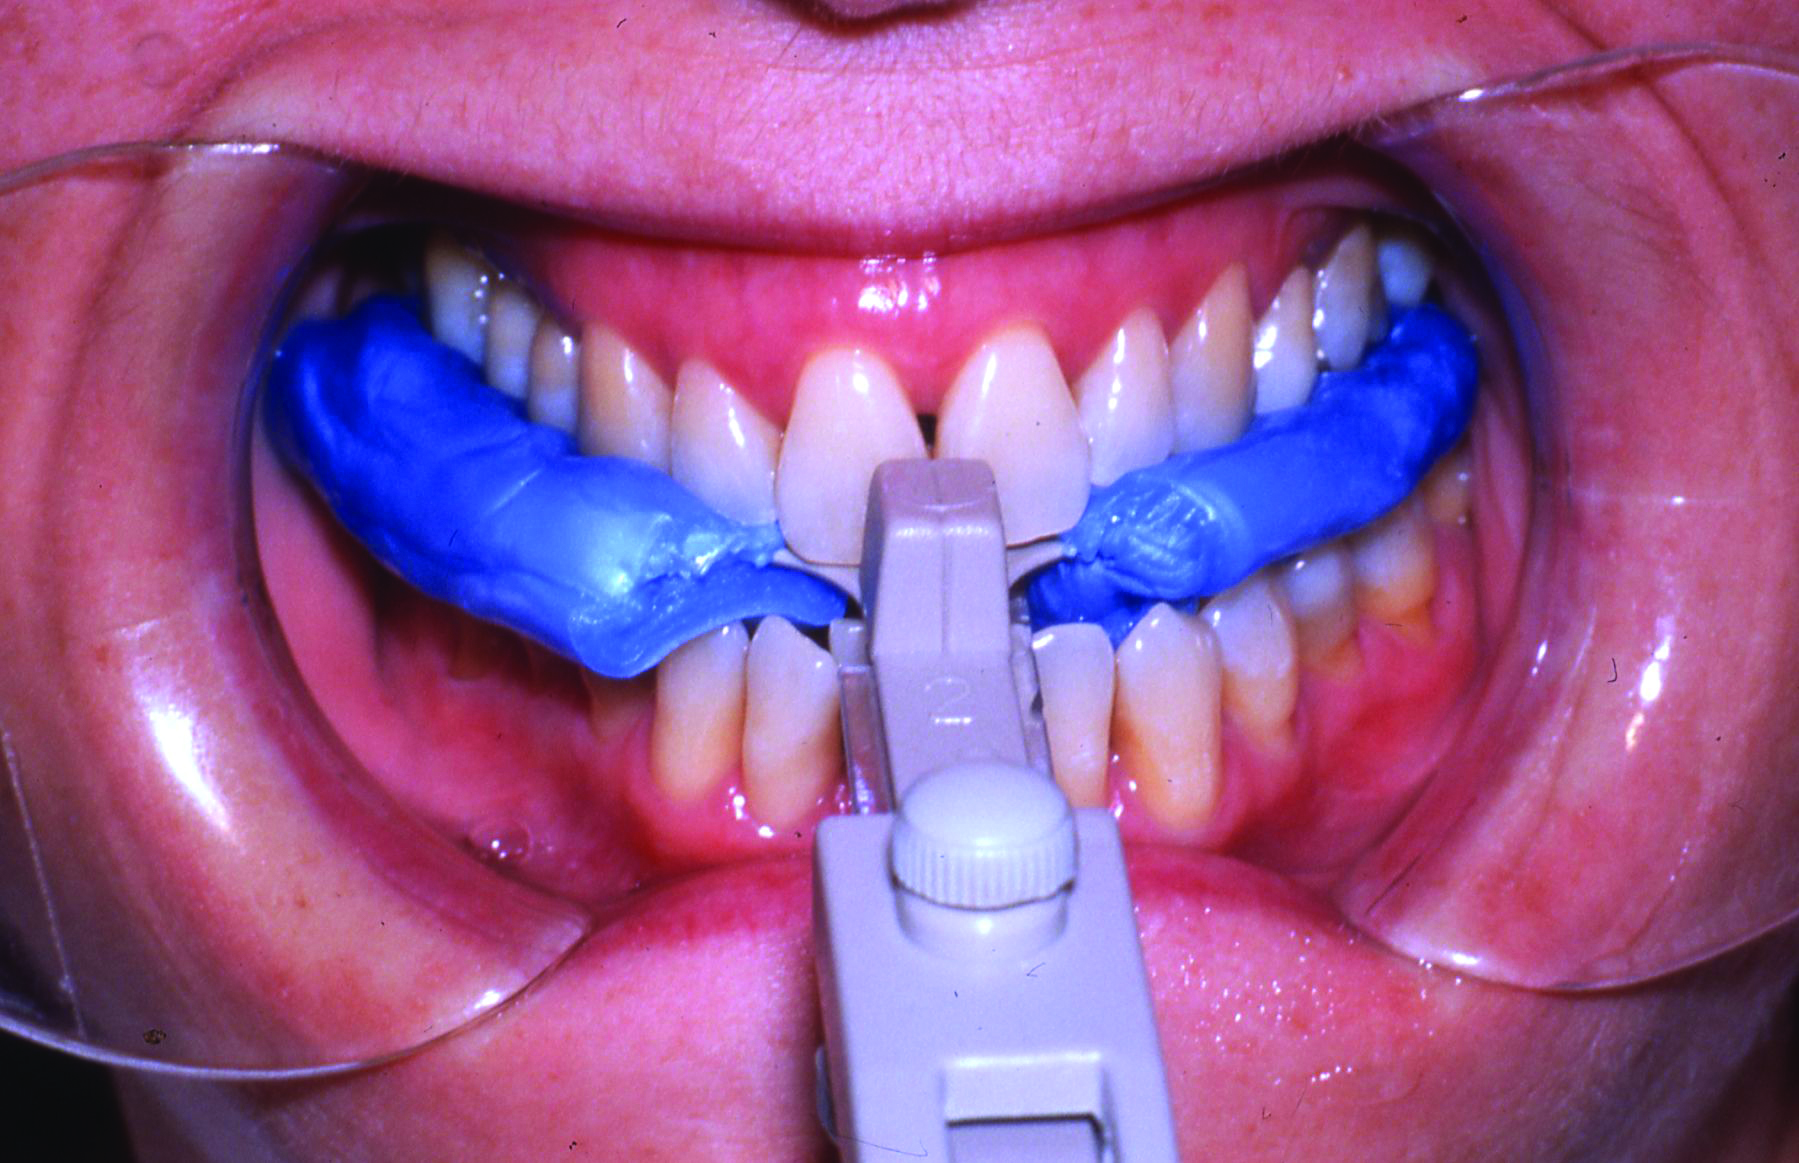

An interocclusal record known as a construction bite is taken to establish the initial jaw advancement of the MAD.3 The construction bite is commonly taken as a percentage (eg, 60-80%) of the patient’s maximum protrusion (Figure 5), a fixed number of millimeters (eg, 3) less than the patient’s maximum protrusion, or at an advanced yet comfortable position of the mandible. Other strategies for taking the construction bite also have been advocated.

Fig 5. Clinical recording of a construction bite. Registration material captures the relationship between the upper and lower teeth when the mandible is held forward using a George Gauge ( http://www.greatlakesortho.com/ ). The MAD is fabricated to hold the jaw in this position when first inserted, before any adjustment.

Fig 5. Clinical recording of a construction bite. Registration material captures the relationship between the upper and lower teeth when the mandible is held forward using a George Gauge (greatlakesortho.com). The MAD is fabricated to hold the jaw in this position when first inserted, before any adjustment.